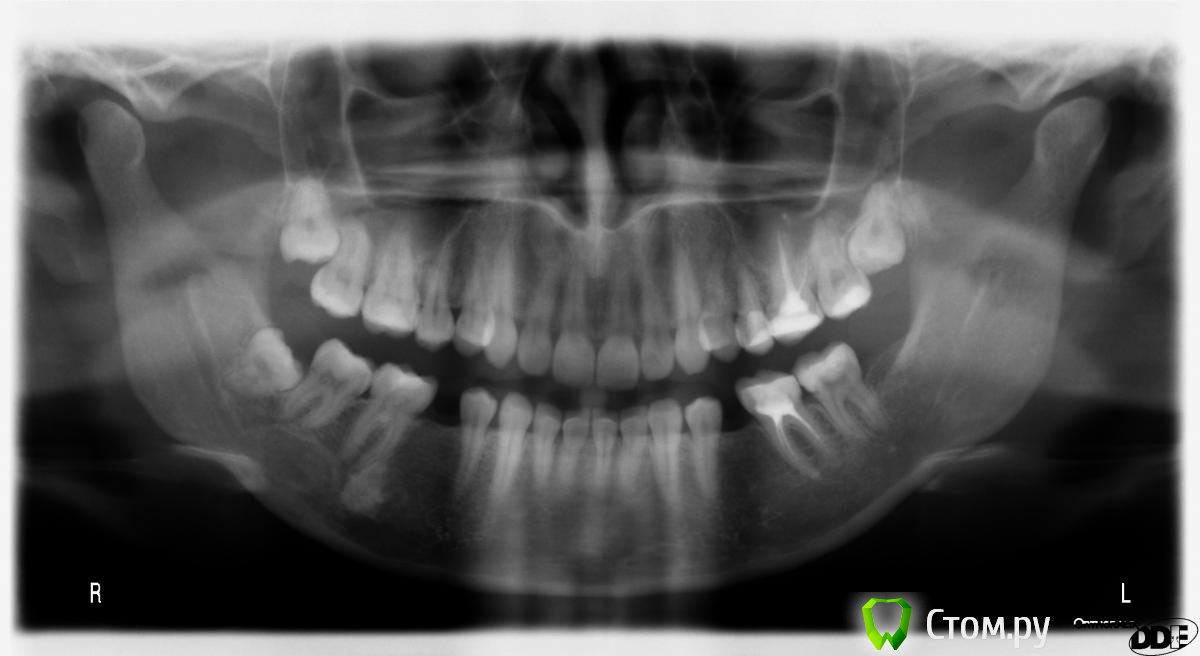

Natalya_msk Опубликовано 23 января, 2014 Поделиться Опубликовано 23 января, 2014 (изменено) Добрый день! Показывала двум врачам, разводят руками, говорят незнают что это... хочу сделать кт.Прикрепляю снимок, может хоть предварительно можно сказать? Белое пятно под 6-м зубом справа. 5-ок никогда не было, были только молочные.Спасибо Изменено 23 января, 2014 пользователем Natalya_msk Ссылка на комментарий

pawa Опубликовано 23 января, 2014 Поделиться Опубликовано 23 января, 2014 конденсирующий остеитлечения не требует Ссылка на комментарий